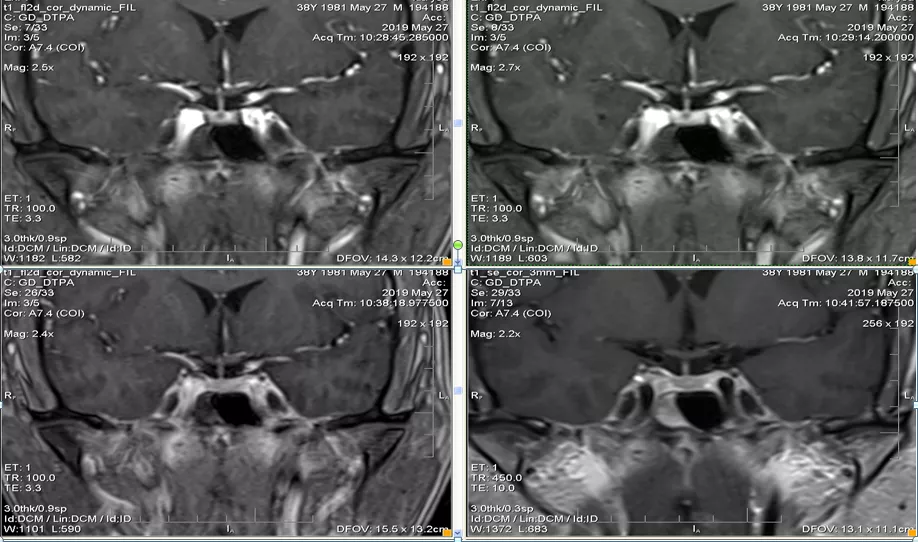

case 7:M/49y 头晕 3D

看完 14 个病例,一起来认识这个表现多样的 Rathke’s囊肿

T1WI 高、T2WI 等信号结节,增强未见强化